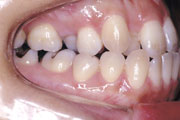

症例1:乱杭歯(叢生)

症例2:乱杭歯(叢生)